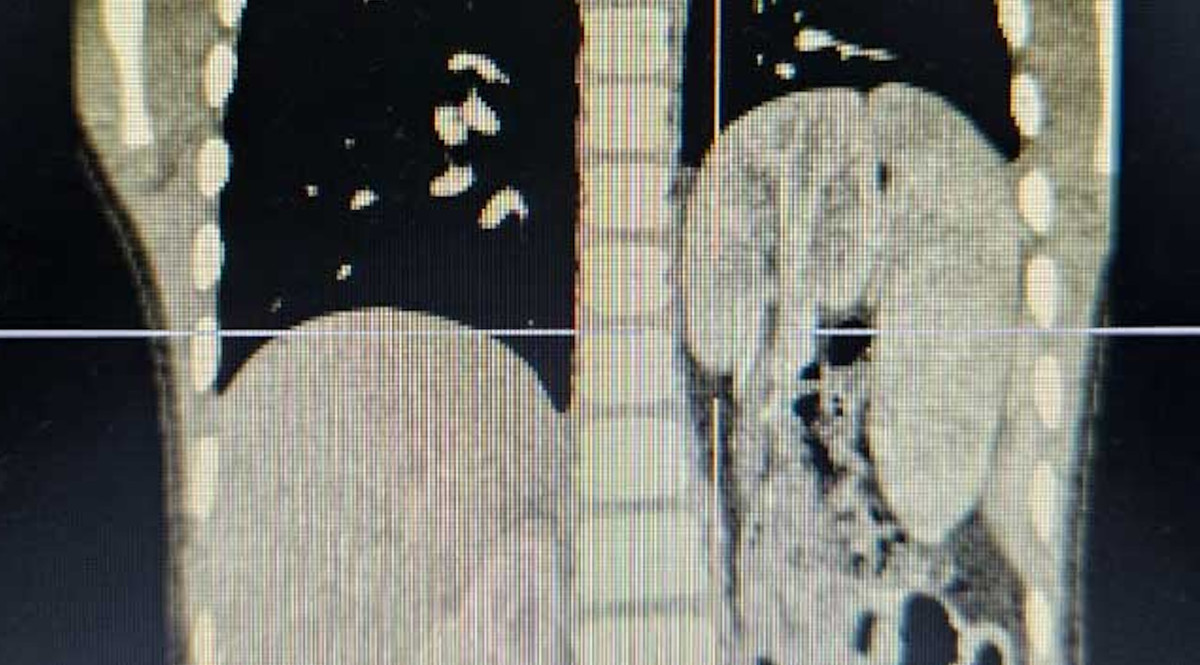

Hình ảnh chụp thoát vị hoành trái bẩm sinh với tạng thoát vị là lách, ruột non, đại tràng và kèm theo thận lạc chỗ trên lồng ngực của trẻ.

Phim chụp cắt lớp vi tính cho thấy các cơ quan thoát vị trở lại vị trí giải phẫu bình thường, cơ hoành liền tốt và phổi trái của bé nở đều. Chức năng thận trái sau khi trở về ổ bụng cũng được đánh giá không có bất thường. Bệnh nhi hồi phục ổn định và được xuất viện sau 7 ngày.